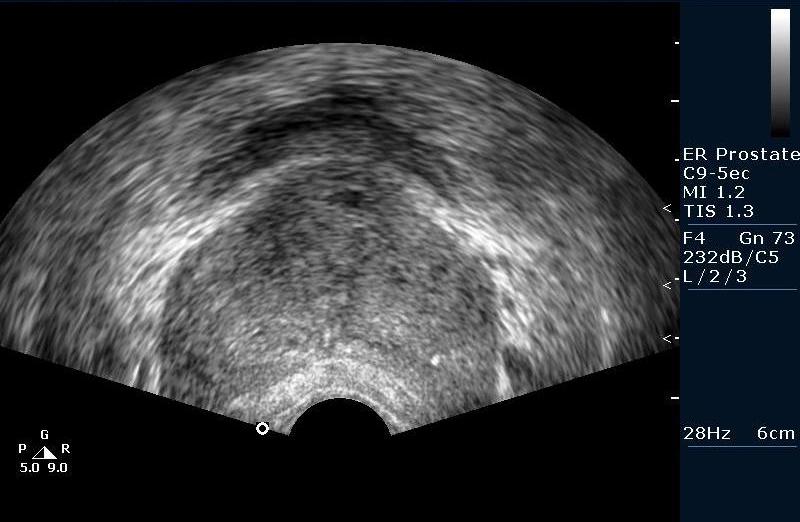

Биопсия предстательной железы под контролем Ультразвуковой визуализации. Рутинная практика в нашем отделении pадиологии, выполняется практически всем пациентам с повышенным уровнем ПСА (естественно, учитывая результаты осмотра урологов).

Предстательная железа